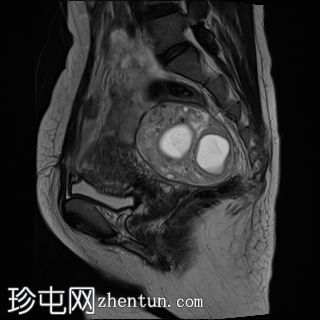

T2加权像

轴位

左侧卵巢增大、水肿,位置异常,卵泡呈周边排列

左侧卵巢血管扭转,呈漩涡征

左侧卵巢实质出血性改变

可见左侧卵巢少量囊肿,内含血信号

未见明显强化软组织肿块

上述左侧卵巢增大、水肿、位置异常、卵泡呈周边排列、实质出血的特征提示卵巢扭转伴出血。梗死。

患者被转诊至妇科医生处,并紧急行输卵管卵巢切除术。病理检查显示广泛的出血性梗死,卵巢包膜下仅残留薄薄一层完整组织。未发现恶性肿瘤